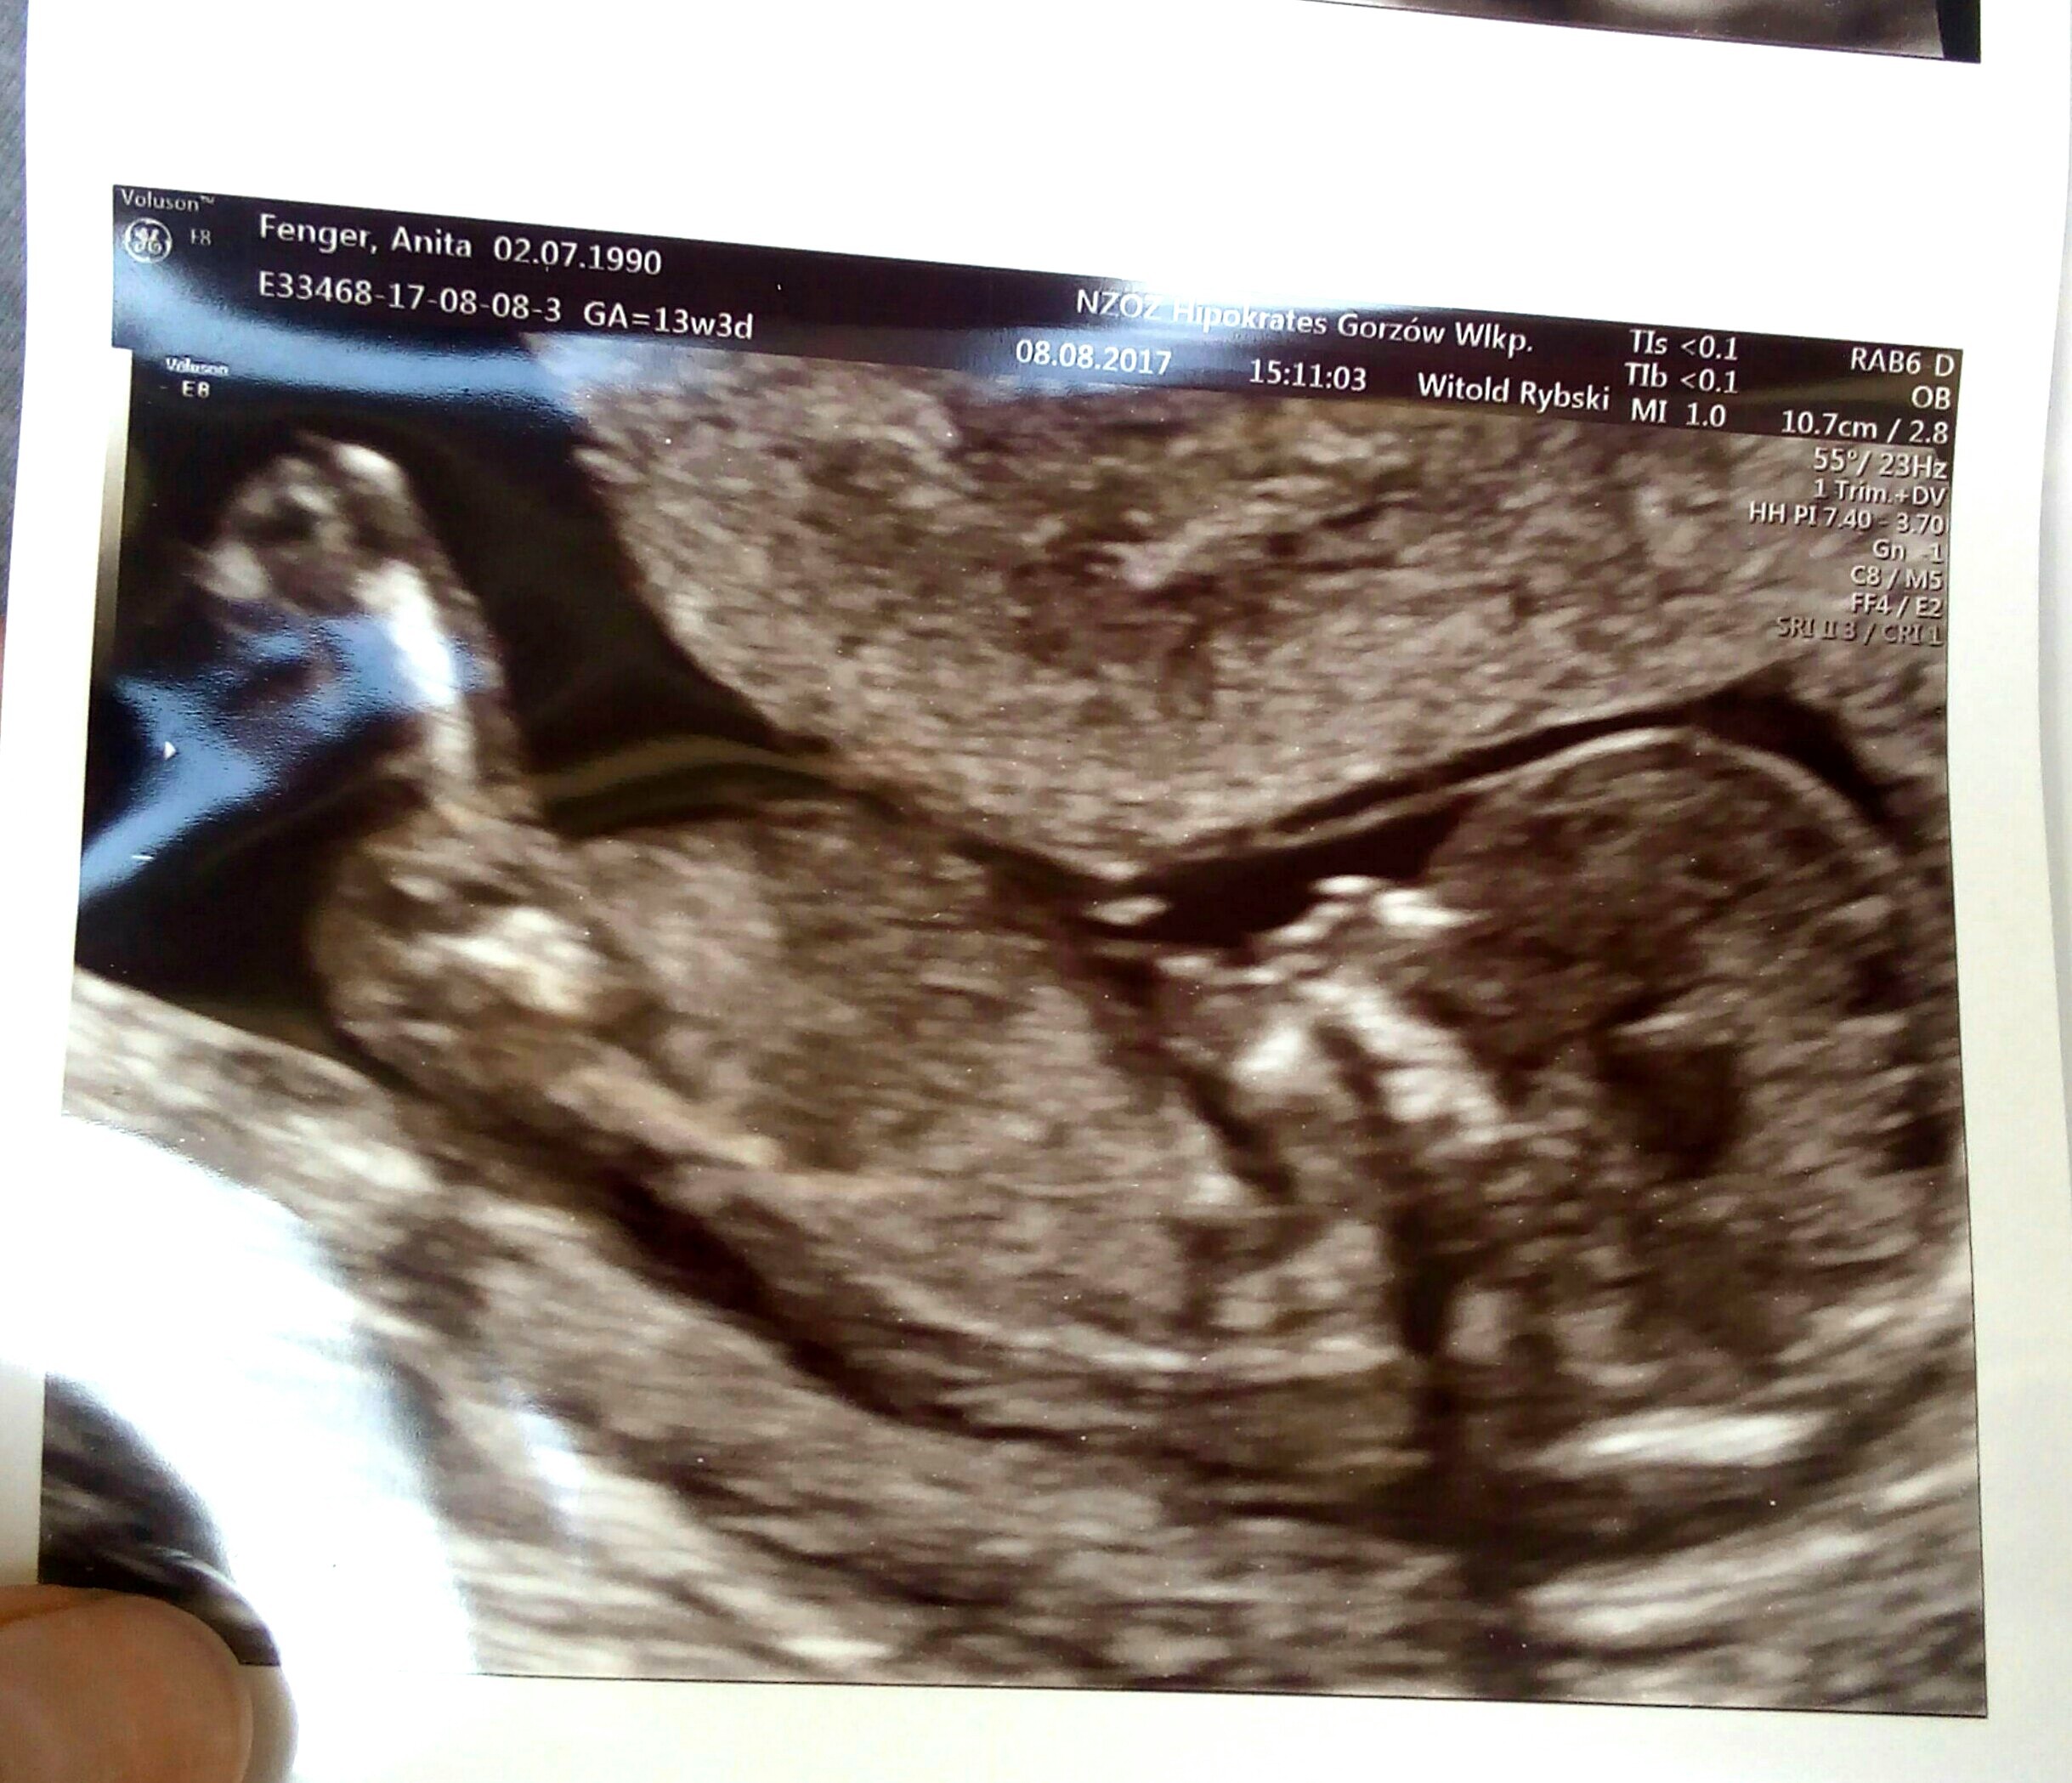

Uff wszystko ok :) dzidzia jadła swoją stopkę ;P ma całe 8,4 cm :) ale nie chciała współpracować i pokazać co ma między nóżkami, cały czas się tyłkiem wypinała ;D